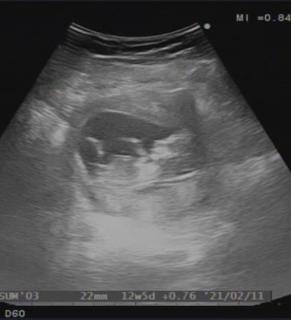

写真:12w1d:りぷとんさん

2022年9月 12w1d 7.5cm

高齢出産なので、NIPT(出生前診断)と胎児ドッグを受けてきました。

小さい手や足を一生懸命動かしていて本当に可愛かった!辛いつわりも吹っ飛びます。もう膀胱でおしっこもちゃんと作られていたり、この段階で分かってしまうのがすごい!9年前の一人目の時よりレベルが上がっていて終始驚いてました笑

12w1d BPD22mm

4日ほど大きく、心拍も鼻の骨や指や大腿骨もしっかりしてピョコピョコ動いてた!もう愛しい!!まだつわりはあるけどお母さんも頑張るよ♪